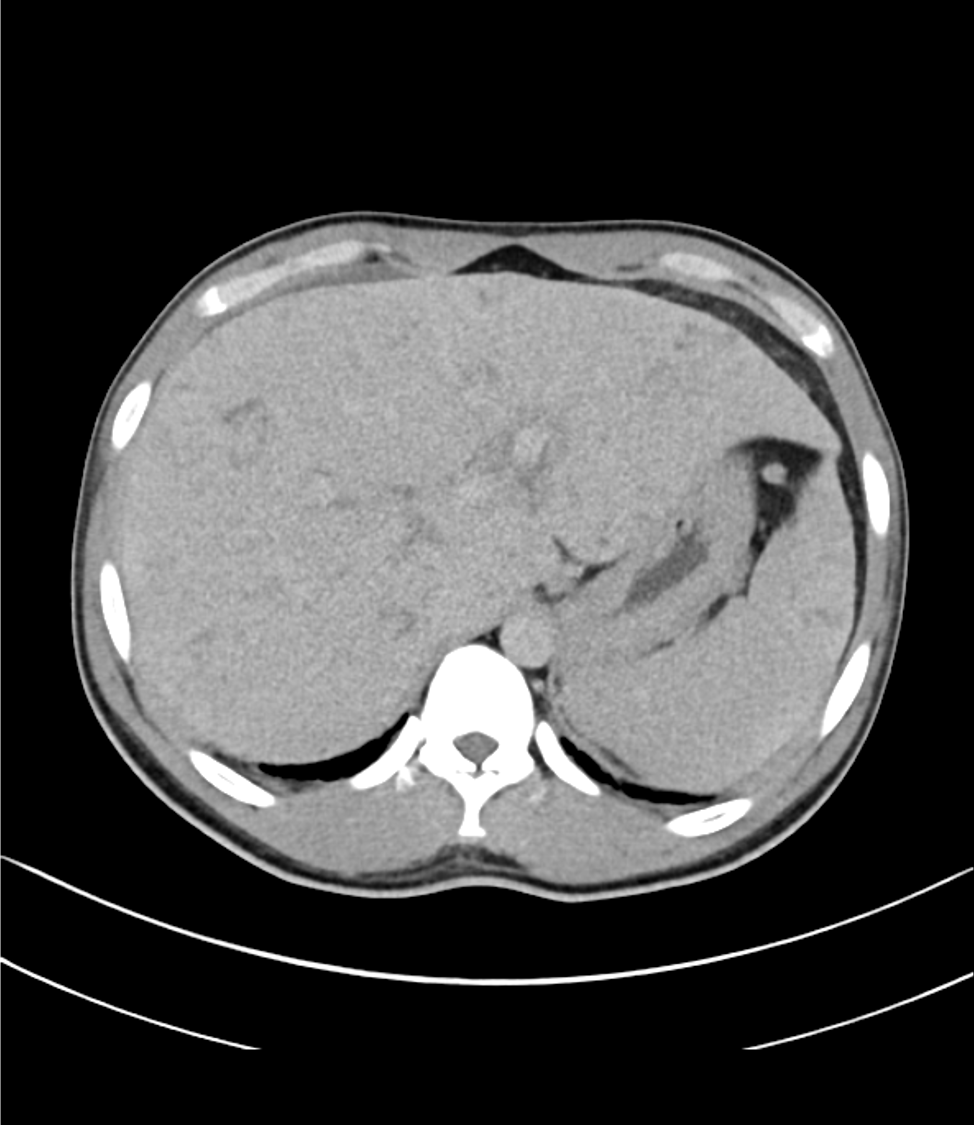

ライギョを加熱不十分で食べたエピソードと、発熱、好酸球増多があり、寄生虫感染が疑われ、精査目的にCTを撮像した。

肝内に地図状の乏血性の領域や、病変内に門脈枝の貫通像がみられ、これらは好酸球増多症における肝病変として矛盾しない所見であった。

好酸球増多症では、肝臓の好酸球浸潤や門脈域を中心とした限局性の壊死が見られる。これらを反映した所見を捉えるのには、ダイナミックCTを撮像することが望ましい。

動脈相では乏血性の領域が見られ、門脈相では最もコントラストが強まる。平衡相では遅延性濃染がみられる。本症例はこれらの所見に合致した。